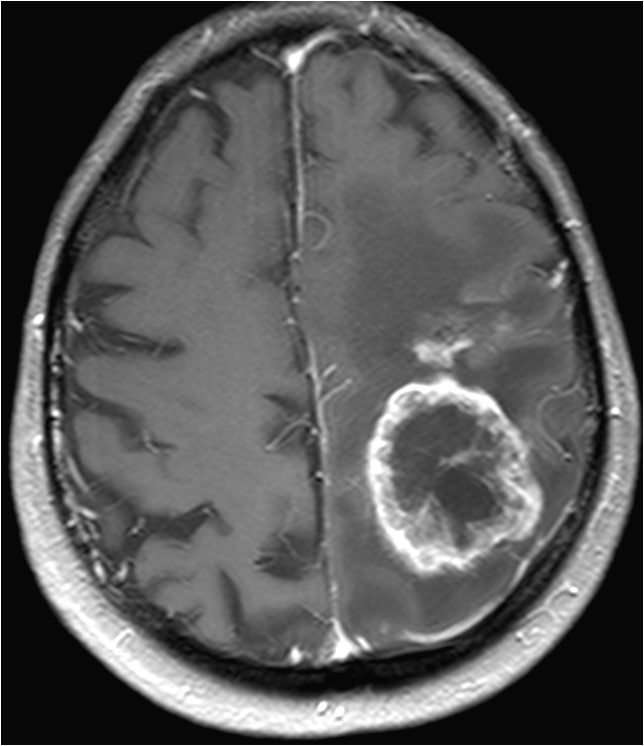

脑肿瘤患者一般有头痛、头晕、呕吐、视力模糊、手脚无力或麻痹等征状,视乎肿瘤所生长位置,病征亦包括癫痫、内分泌失调、甚至性情及行为改变等。现今的脑扫描技术已相当发达。计算机扫描和磁力共振是最常采用的诊断仪器。

磁力共振不涉及辐射危险性,只需要病人躺卧在具有强大磁场的仪器上进行扫描,过程中病人不会感觉痛楚。磁力共振影像可作多个不同角度和透过不同「拍摄」方法,取得肿瘤的多项影像参数,从而让脑神经外科医生为病人作出最合适的治理方案。